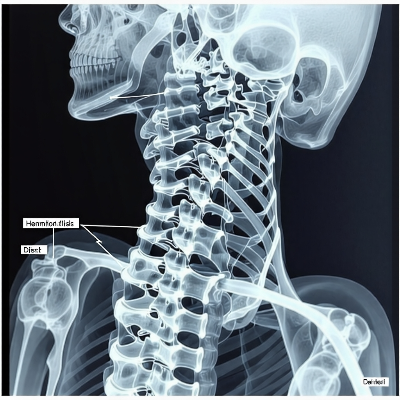

목 디스크는 현대인들에게 흔한 건강 문제로, 잘못된 생활 습관이 주요 원인으로 꼽힙니다. 이번 글에서는 목 디스크의 원인을 분석하고, 증상과 효과적인 치료법에 대해 자세히 알아보겠습니다.

목 디스크의 증상은 다양한 형태로 나타날 수 있으며, 초기에는 가벼운 통증으로 시작되는 경우가 많습니다. 대표적인 증상으로는 목이나 어깨 부위의 뻣뻣함, 통증, 그리고 팔이나 손가락으로 이어지는 저림 현상이 있습니다. 심한 경우 목을 움직이는 것조차 어려워질 수 있습니다. 팔의 감각 저하나 힘이 빠지는 증상도 주의해야 합니다. 이러한 증상은 디스크가 신경을 압박하여 발생하며, 특정 자세를 취했을 때 증상이 심화되기도 합니다. 만약 증상이 지속되거나 악화된다면, 반드시 전문의의 진단을 받아야 합니다. 자가진단을 위해서는 자신의 생활 습관을 점검하는 것이 중요합니다. 목을 숙인 자세가 장시간 유지되는지, 운동 부족으로 인해 근력이 약해졌는지 확인해 보시기 바랍니다. 증상이 의심될 경우 조기 치료를 통해 상태를 악화시키지 않도록 해야 합니다.

크게 수술적 방법과 비수술적 방법으로 나뉩니다. 일반적으로 초기 단계에서는 비수술적 치료가 주로 시행됩니다. 가장 흔한 방법은 약물치료와 물리치료입니다. 약물치료는 통증과 염증을 완화하기 위해 진통제와 근육 이완제를 처방하며, 물리치료는 목 근육을 강화하고 유연성을 높이는 데 효과적입니다. 또한, 견인치료와 같은 비수술적 접근법도 많이 활용됩니다. 견인치료는 척추의 간격을 넓혀 디스크가 신경을 압박하는 것을 줄여줍니다. 이와 함께 전문적인 도수치료와 재활운동도 환자의 회복을 돕습니다. 그러나 비수술적 방법으로도 증상이 호전되지 않는다면, 수술적 치료가 필요할 수 있습니다. 디스크 제거술이나 인공 디스크 치환술 등은 신경 압박을 완화시키고 통증을 줄이는 데 매우 효과적입니다. 다만, 수술은 신중하게 고려해야 하며 전문의와 충분한 상담 후 결정해야 합니다.